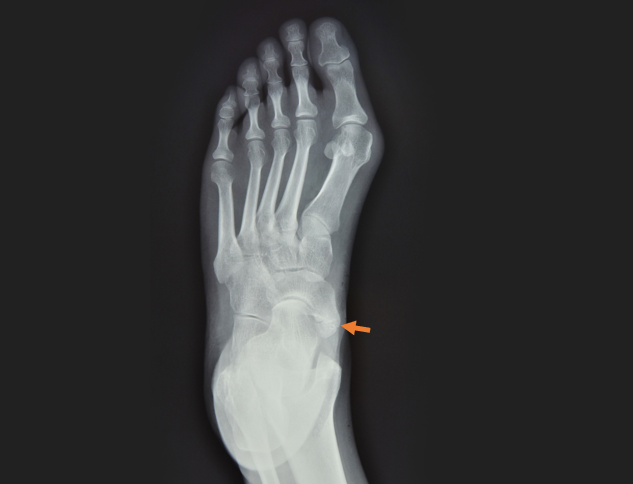

Dodatkowa kość łódkowata

Kość łódkowata jest najczęściej występującą kością dodatkową w obrębie ludzkiej stopy. Znajduje się po stronie przyśrodkowej stępu w okolicy przyśrodkowej kości łódkowatej. Może pojawić się zarówno tylko w jednej, jak i w obu stopach. Czasami objawy nie są spowodowane obecnością kości łódkowatej dodatkowej, lecz przerośniętą guzowatością kości łódkowatej.

Jednakże, niektóre osoby w okresie dojrzewania, wyczuwać mogą guza po stronie przyśrodkowej stępu. Zmiana ta może być bolesna i może wywoływać utrudnienia w doborze obuwia. Czasami połączenie więzozrostowe pomiędzy kością łódkowatą i kością łódkowatą dodatkową może stać się bolesne po urazie (najczęściej urazie skrętnym). W takim przypadku dolegliwości są zwykle duże i mają charakter przewlekły. Rozpoznanie stawia się na podstawie badania radiologicznego, niekiedy wspartym przez badanie TK lub rezonansu magnetycznego.

Rozróżnia się trzy typy tej choroby:

- Typ I jest przeważnie asymptomatyczny. Jest to niewielka kostka dodatkowa położona ku tyłowi;

- Typ II to wyraźna kostka dodatkowa w przedłużeniu kości łódkowatej;

- Typ III to przerośnięta kość łódkowata, przyjmująca kształt rogu.